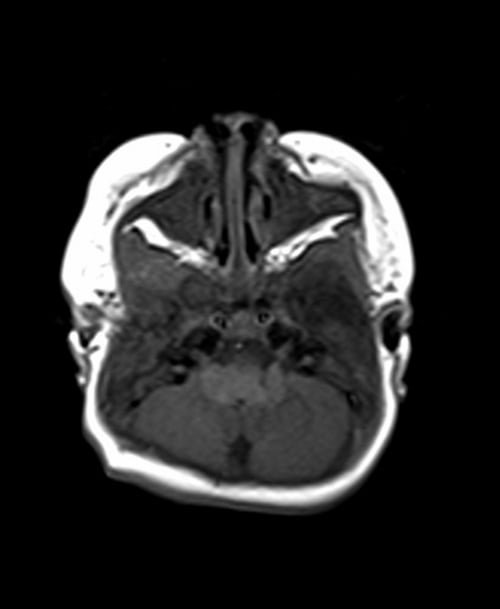

MRI pediatric brain axial T1 images